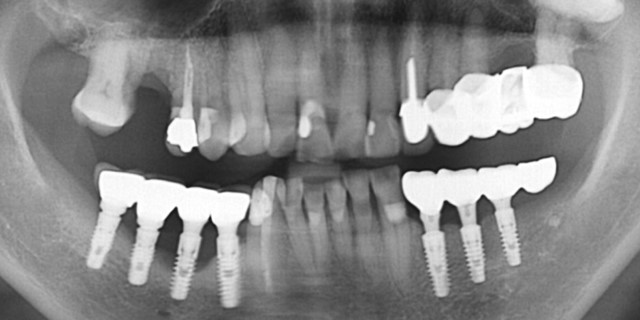

±¸Ä¡ºÎ ´ÜÀÏ ÀÓÇÁ¶õÆ®´Â ÃÖ¼ÒÇÑ Áö¸§ÀÌ 4.5mm 4.8mm, 5.0mm ÀÌ»óÀÇ °ÍÀ» »ç¿ë

2) Sinking(sink down, ħÇÏ)

´ë±¸Ä¡ºÎ, ƯÈ÷ 7¹ø ½Ì±ÛÀº À§ÇèÇÏ´Ù. ¶ÇÇÑ 6¹ø ½ÉÀ» ¶§ M-D distance(¾Õ-µÚ Æø°æ)°¡ 12mm Âë ³ª¿Í¼ 2°³ÀÇ ÇȽºÃÄ´Â ¸ø ½É°í ÇÑ °³ ½É¾î¼ ÇØ°áÇÏ´Â °æ¿ì¿¡ ƯÈ÷

Á¶½ÉÇØ¾ß ÇÑ´Ù.

ÇȽºÃĵµ Âõ¾îÁú ¼ö ÀÖ°í, ¾î¹þ¸ÕÆ®µµ ºÎ·¯Áú ¼ö ÀÖ´Ù. ¶ÇÇÑ ³ª»ç Ç®¸²µµ ¸¹ÀÌ ¹ß»ýÇÑ´Ù. ÀÌ·± Ưº°ÇÑ °æ¿ì¿¡µµ EZC¿Í °°Àº convertible abutment°¡ À¯¸®ÇÏ´Ù.